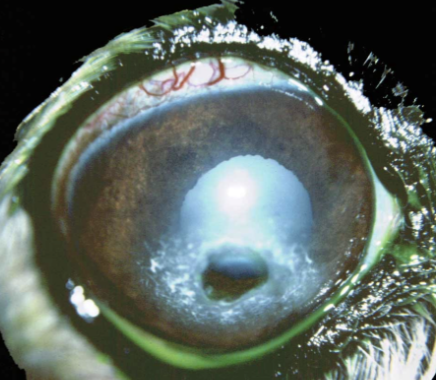

recognising corneal perforation

Acutely painful

yelp in pain, keep eye completely closed

Excessive ‘tearing’ or wetting of the face below ulcer

Perforation site often plugged with clotted aqueous (+/- haemorrhage)

iris Appears as tan, red or pigmented bulging mass at the centre of an ulcer

—>Refer as an emergency for corneal graft or enucleate